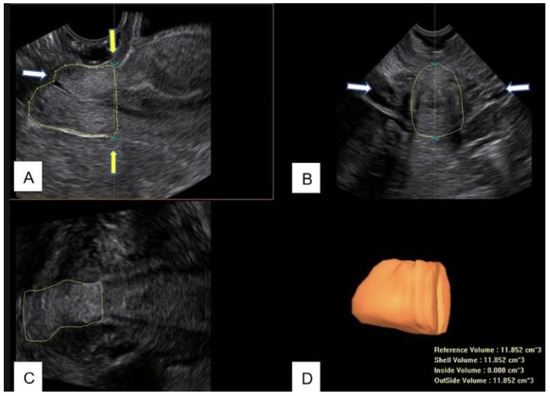

2.4. Cone Measurements

- Dückelmann, A.M.; Wordell, J.; Richter, R.; Sehouli, J. 3D ultrasound as a surgical quality control of conization in patients with severe dysplasia: A prospective study. Arch. Gynecol. Obstet. 2020, 302, 1189–1196. [Google Scholar] [CrossRef]